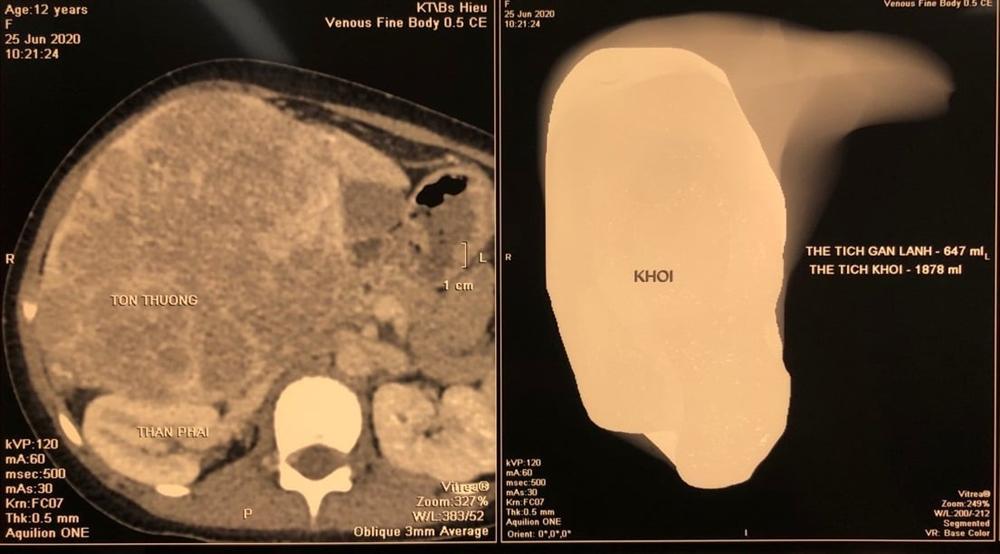

Khối u buồng trứng khổng lồ có kích thương tương đương thai 7 tháng. Ảnh: BVCC.

Bụng ngày càng to nhưng bệnh nhân quyết định không đi khám. Bà cho rằng mình làm việc nhiều nên tức bụng do đói, ăn khỏe hơn dẫn đến tăng cân. Sau khi được mọi người xung quanh khuyên, người này mới đến khám tại bệnh viện địa phương và được chuyển thẳng tới Bệnh viện Ung Bướu Hà Nội do nghi ngờ ung thư. Tại đây, kết quả xét nghiệm cho thấy ổ bụng của bà A. có khối u kích thước 20x30 cm.